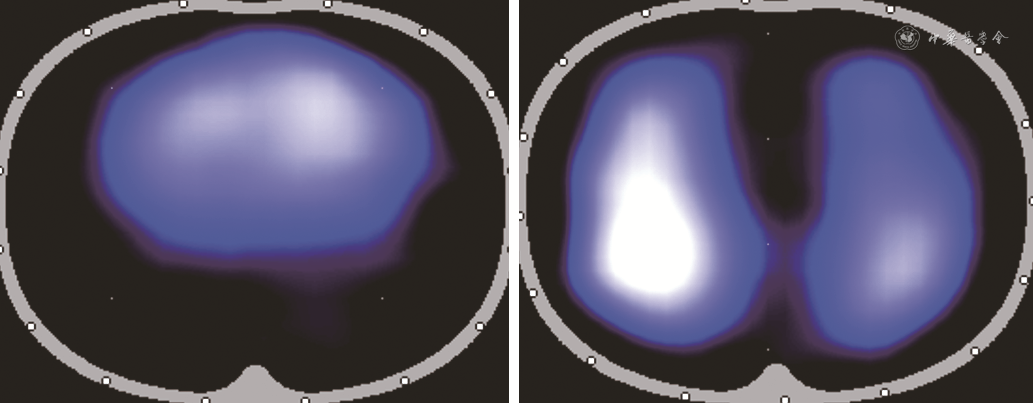

推荐意见3:肥胖可导致EIT肺通气图像呈“左右肺融合单一类圆型轮廓”,但不影响EIT连续动态的肺通气监测能力。[推荐强度:(7.35±1.31)分]

肥胖患者[体质指数(body mass index,BMI)>30 kg/m2]由于胸廓脂肪密度增高且分布不均、双侧胸壁电阻增加等因素可以影响EIT通气图像的建构。肥胖患者的肺通气图像可表现为左右肺融合单一样类圆形通气区域,而非常见的左-右侧肺通气的轮廓区域(图1)。因此,临床在解读非胸廓畸形出现的肺通气“左右肺融合样畸形轮廓”分布,在排除胸腔实质性病变后,需要考虑到肥胖因素的可能。部分EIT设备建议肺通气显像不能应用于BMI>50 kg/m2的患者。但需要指出的是,虽然肥胖可能导致EIT通气图像轮廓异常,但并不影响其反映肺通气的能力,可用于连续动态监测肺通气功能。临床研究支持EIT可用于监测肥胖患者(BMI:39~60 kg/m2)胃减容术围手术期的肺容积变化、机械通气个体化PEEP设置以及高流量氧疗等呼吸管理[11, 12, 13]。

注:BMI为体质指数;EIT为电阻抗成像